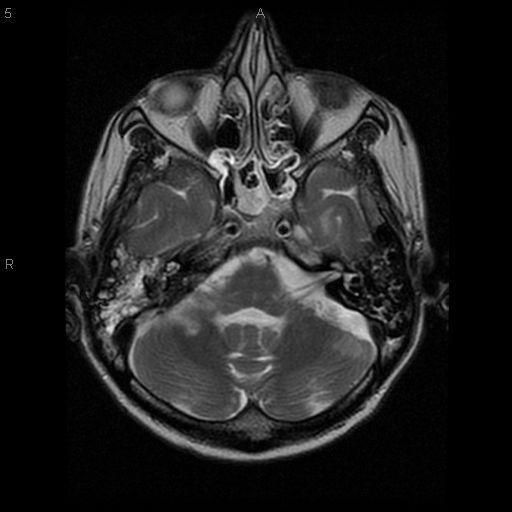

We report a fatal case of meningitis, caused by Fusobacterium necrophorum, secondary to otitis media in an alcoholic male. Diagnosis was delayed due to the typical slow growth of the organism. The clinical course was complicated by encephalitis and by hydrocephalus. The patient failed to respond to metronidazole and penicillin. The patient died on day 12 from increased intracranial pressure and brain stem infarction.

我们报告一例由坏死梭杆菌引起的致命性脑膜炎病例,该病例继发于一名酗酒男性的中耳炎。由于该病菌典型的缓慢生长特性,诊断被延误。临床过程因脑炎和脑积水而复杂化。患者对甲硝唑和青霉素治疗无反应。患者于第12天因颅内压升高和脑干梗死死亡。